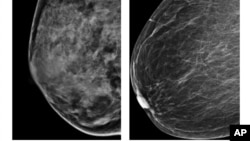

Esta radiografía del American College of Radiology muestra un pecho extremamente denso (izquierda) y otro menos denso. Un estudio ha descubierto cuatro tipos de cáncer de mama por lo que los tratamientos deben ser diferentes.

El estudio ha identificado cuatro tipos de cáncer de pecho importantes, uno de los cuales tiene moléculas similares al cáncer de ovario.